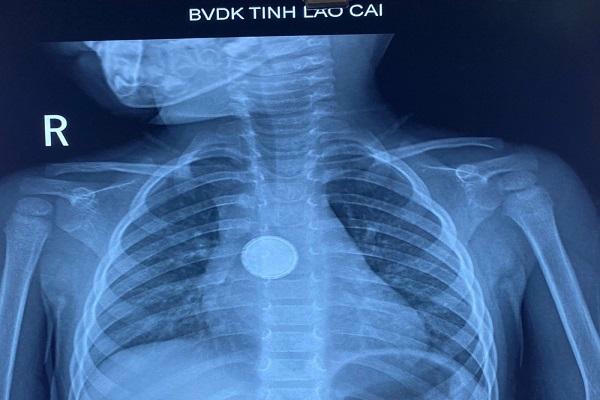

Qua hình ảnh phim chụp X-quang cho thấy vị trí dị vật tương đương ngã ba chỗ chia khí quản gốc phải và gốc trái. Các bác sỹ đã tiến hành hội chẩn và xác định dị vật ở vị trí rất khó can thiệp do bệnh nhi dễ kích thích, co thắt liên tục, dẫn đến suy hô hấp và có thể tử vong.

Bệnh nhi bị hóc dị vật thực quản là một chiếc pin cúc áo với đường kính gần 2 cm. Ảnh: TL |